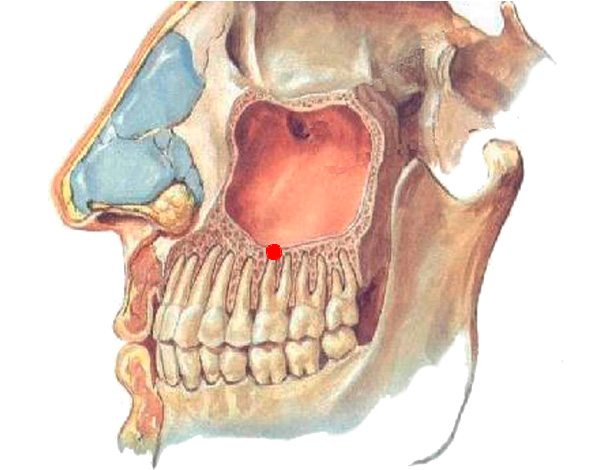

O que é um cisto dentário? O cisto radicular do dente é uma neoplasia localizada principalmente no ápice da raiz e é uma espécie de cápsula, cujo interior da concha contém líquido. Sob certas condições patológicas, o cisto é capaz de crescer com o tempo, aumentando de tamanho.

No processo de seu desenvolvimento, o cisto dentário passa por 2 estágios de periodontite, nos quais, inicialmente, ocorre uma rarefação do tecido ósseo da mandíbula próximo ao ápice da raiz com bordas nebulosas e, somente então, devido à intensa deterioração dos tecidos saudáveis, granuloma, cisto granular e (ou) um cisto com limites claros são formados.

- Germinação de tecido cisto no seio maxilar;

A foto abaixo mostra um exemplo de um cisto enorme, que não foi removido em tempo hábil e, tendo aumentado em volume, cresceu até as raízes de um dente adjacente:

É difícil determinar com uma imagem objetiva e mesmo com uma tomografia computadorizada com 100% de precisão que forma do processo inflamatório está presente na (s) raiz (s) do dente. Área de iluminação geralmente visível com contornos claros, geralmente arredondados ou ovais. Esse "círculo" pode ser localizado não apenas em uma raiz, mas também captura 2-3 raízes de um dente e até mesmo passa nas proximidades imediatas do topo das raízes dos dentes adjacentes, sugerindo ao dentista a escala da tragédia.